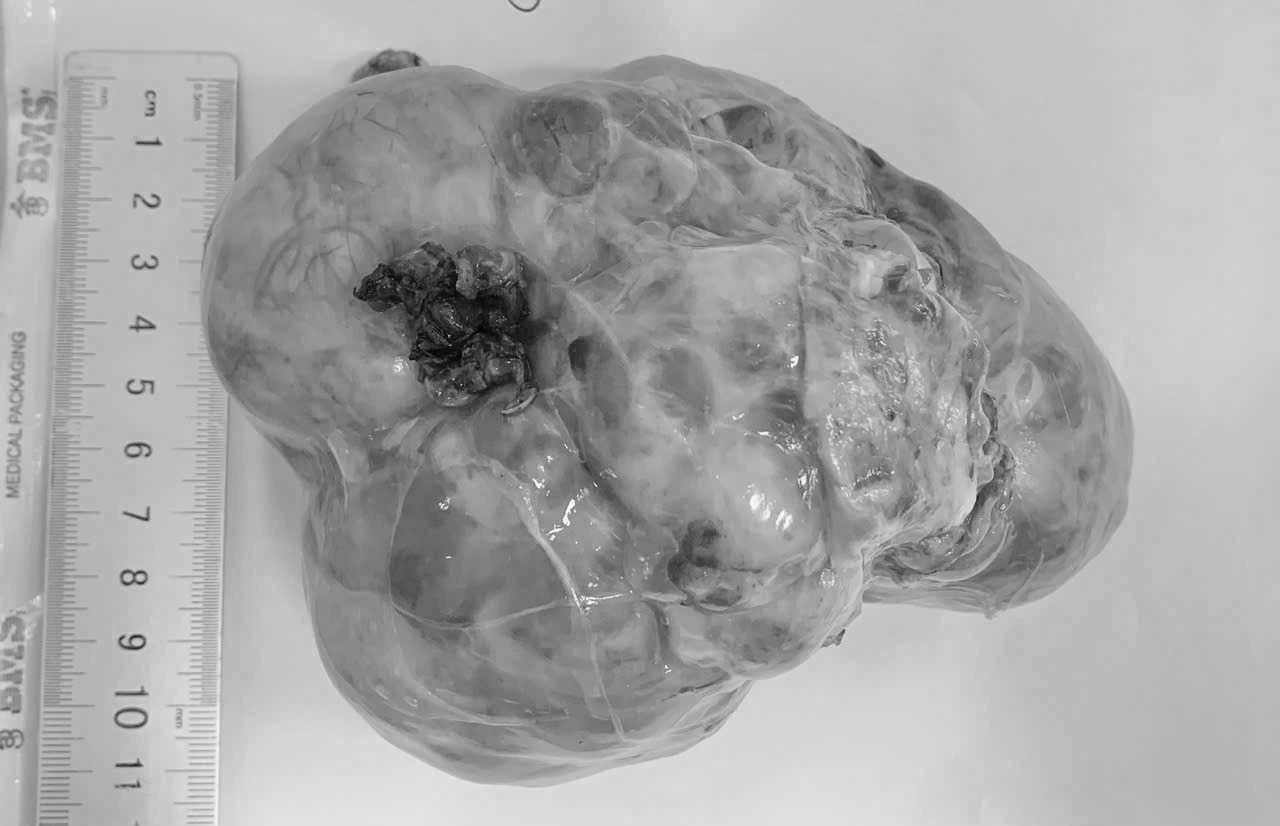

Khối u ổ bụng được phát hiện khi đã phát triển lớn ở bệnh nhi

Theo các bác sĩ, điểm chung đáng lo ngại là 3 trường hợp đều được phát hiện khi khối u đã phát triển lớn, gây chèn ép các cơ quan trong ổ bụng, khiến việc phẫu thuật trở nên phức tạp, đồng thời làm tăng nguy cơ phải điều trị phối hợp nhiều phương pháp sau mổ.